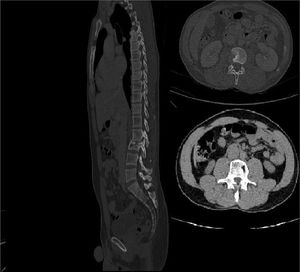

After 24 weeks, bedaquiline was interrupted and replaced with Moxifloxacin (MXF) 400 mg daily. The patients continued treatment with MXF, LZD, and RFB, for another year, without any adverse effect. At the end of treatment, we performed another CT (Fig. 3) that showed complete healing.